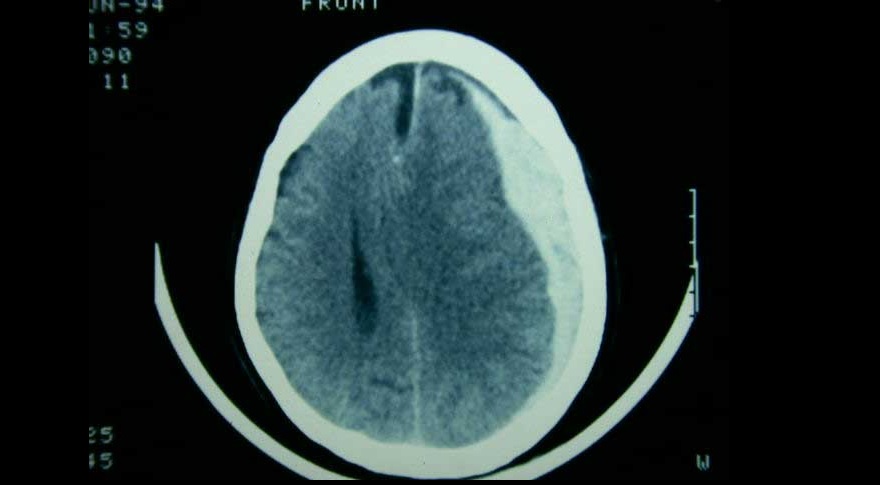

Evacuación inicial o tratamiento conservador en el hematoma subdural agudo

El tratamiento de pacientes con hematoma subdural agudo difiere según el centro de tratamiento, debido a la variación en el abordaje preferido. Una estrategia de tratamiento que prefirió un enfoque agresivo de evacuación quirúrgica aguda sobre el tratamiento conservador inicial no se asoció con un mejor resultado funcional. The Lancet Neurology, 5 de mayo de 2022.